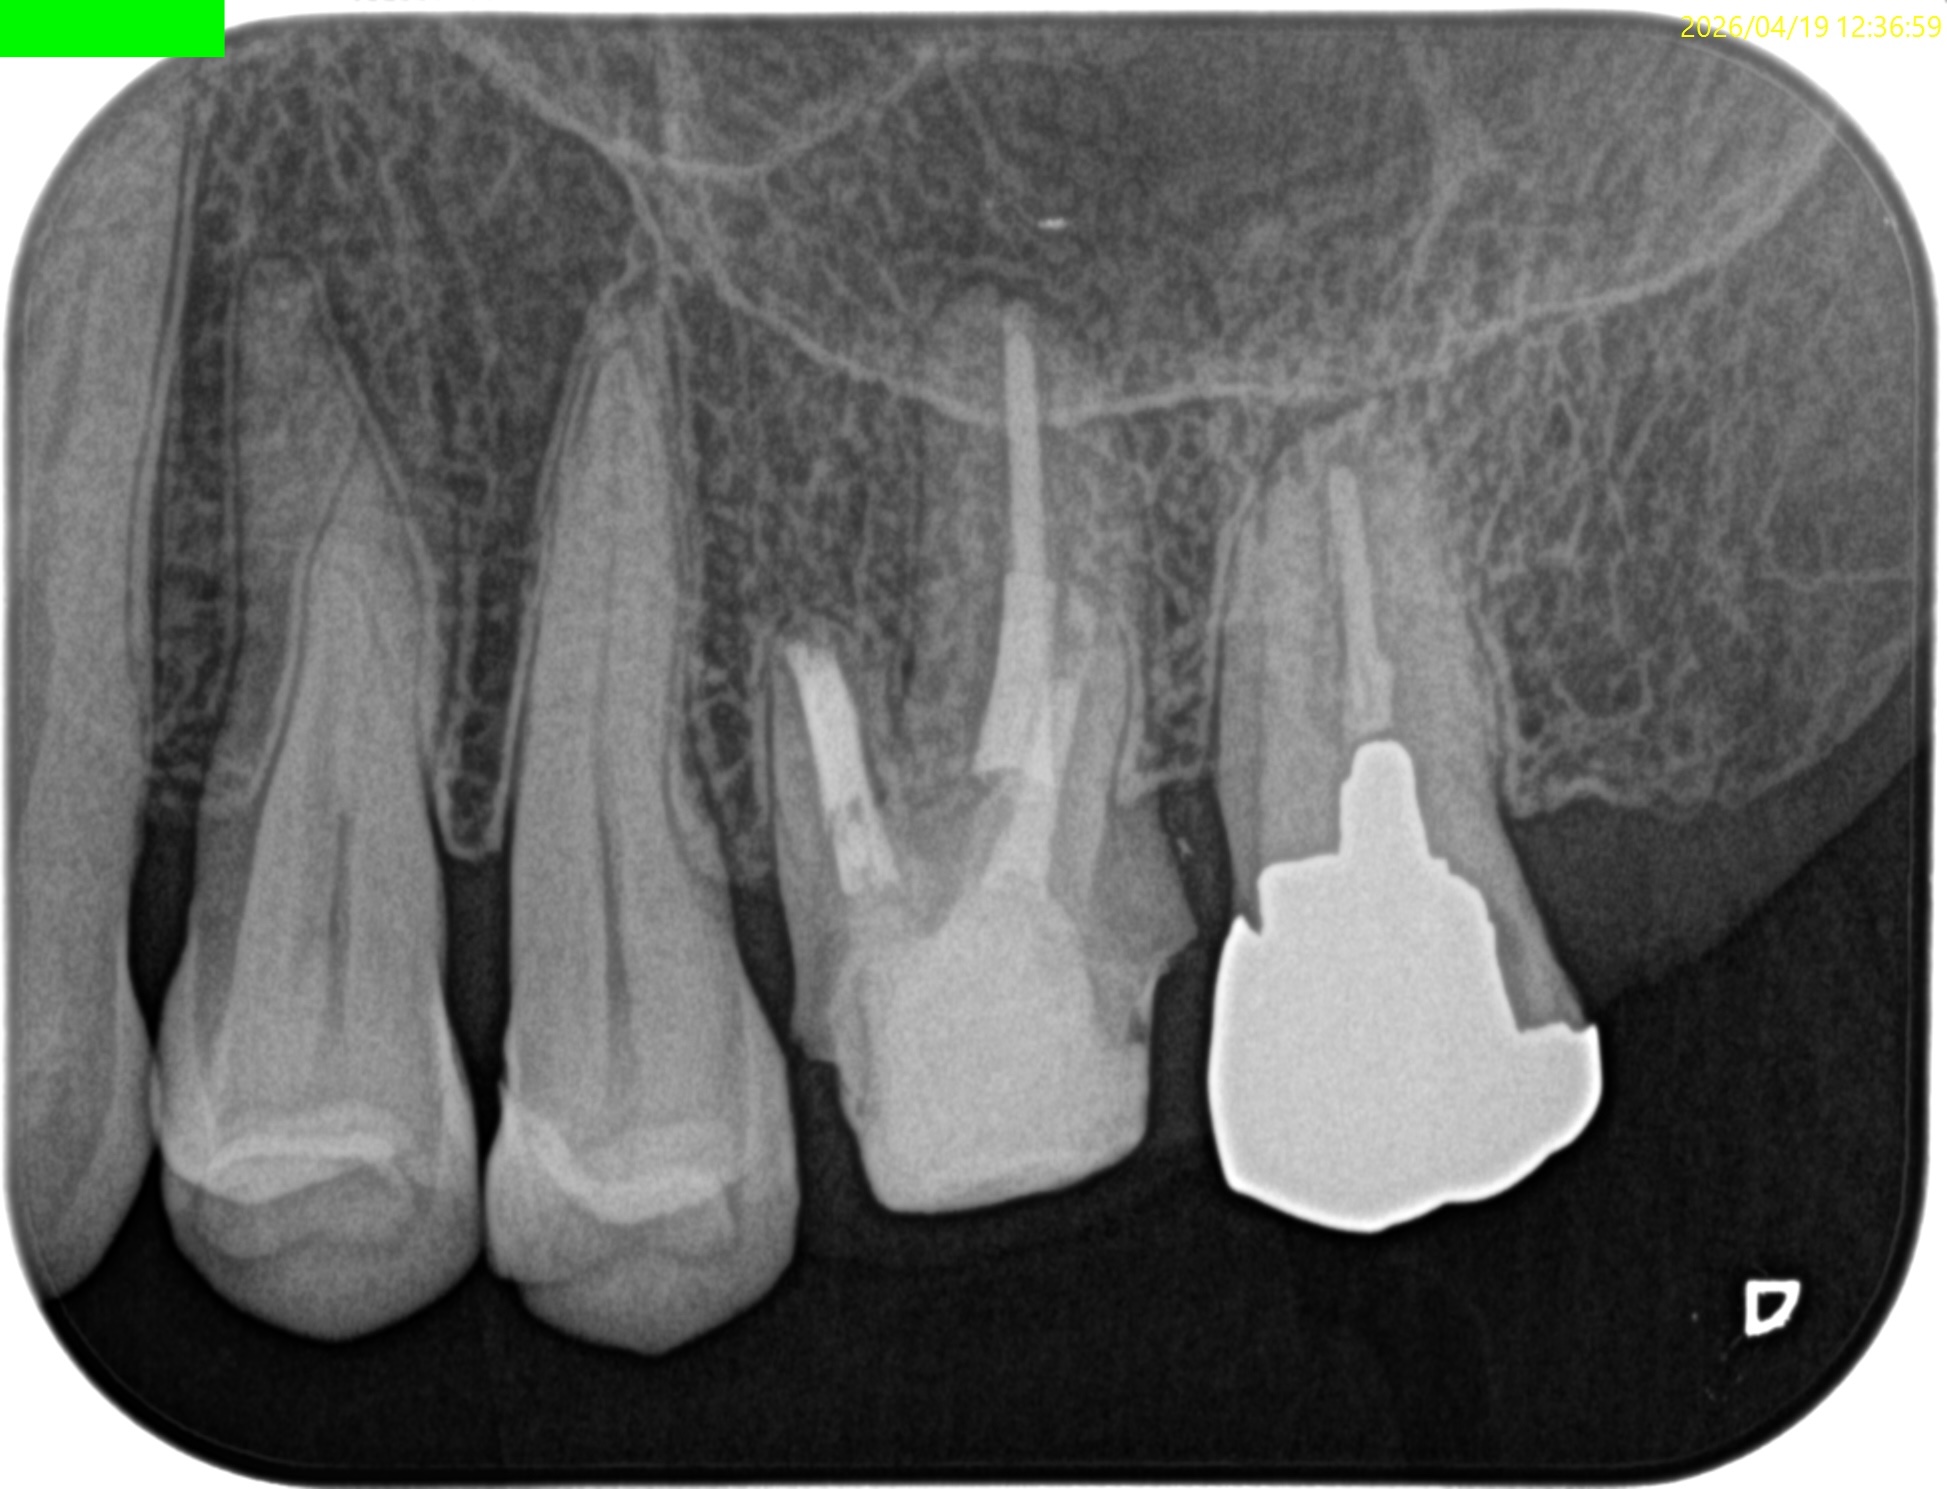

#14 Post-op 2yr recall(2026.4.19)

初診時と比較した。

歯槽骨の欠損は完治した。

術前の臨床症状も消失した。